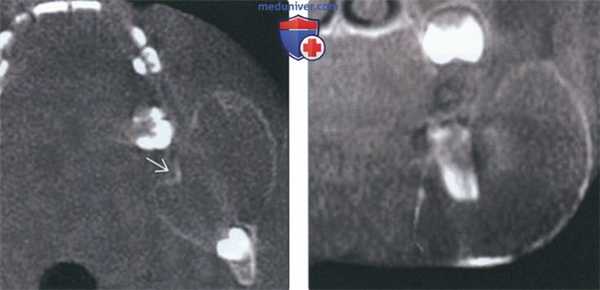

(Слева) На аксиальной КЛКТ у этого же пациента визуализируется АФ. Кортикальная пластинка вздута и истончена, но не перфорирована. Обратите внимание, что края опухоли соединяются с нормальной кортикальной пластинкой под острым углом, что характерно для опухоли, но не для кисты, приводящей к гидравлической экспансии и переходящей в кортикальную пластинку под более тупыми углами.

(Справа) На корональной КЛКТ у этого же пациента определяется АФ, приводящая к вздутию преимущественно щечной кортикальной пластинки.